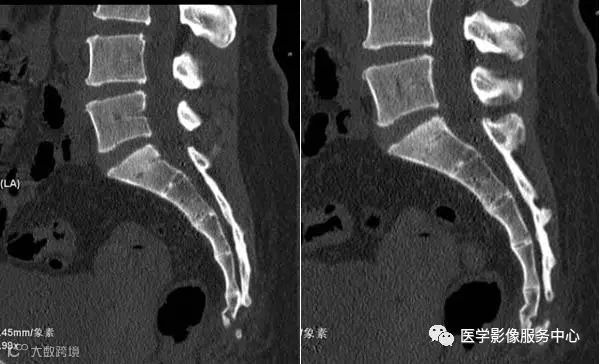

病人女性,外伤后骶尾部疼痛,dr片示骶尾关节对应关系差,骶5椎体欠规则。ct重建示骶5椎体粉碎性骨折!

CT